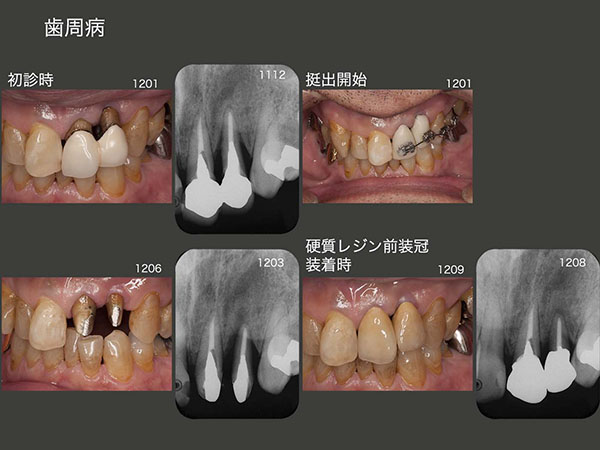

4.歯周病

2012年1月初診,58歳の男性.左上2に7mmの歯周ポケットが認められ,またデンタルX線写真から垂直性の骨欠損がみられた.通常は連結されている冠を外し,自然挺出を行うのが望ましいが,早期の治療を望まれたため,12年1月,矯正的挺出を開始し,6月終了した.9月に硬質レジン前装冠を装着した.なお,左上2の動揺が想像していたより少なかったので,清掃性を配慮し単独冠にした.装着後のデンタルX線写真から,おおむね歯槽骨の平坦化が確認できた.

しかし17年6月の時点で,左上2の歯周ポケットは3mm以下であるが,動揺が大きくなってしまったので,左上1とスーパーボンドで固定した.最初から連結固定するべきであったと反省している.